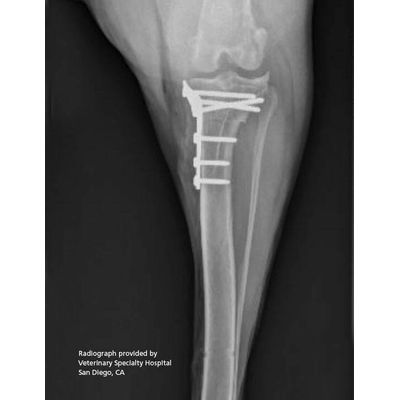

Securos - Tibial Plateau-Leveling Osteotomy (TPLO) System

TPLO provides some of the best outcomes for stifle stabilization in cruciate-deficient dogs. We offer two lines of TPLO plates—patented conventional (non-locking) stainless steel plates, and a polyaxial locking plate and screw system (PAX). Made of biocompatible titanium alloy, our PAX plates and screws feature a crescent head to accommodate high tibial osteotomies, and a proximocaudal curve to optimize plate alignment and screw purchase.